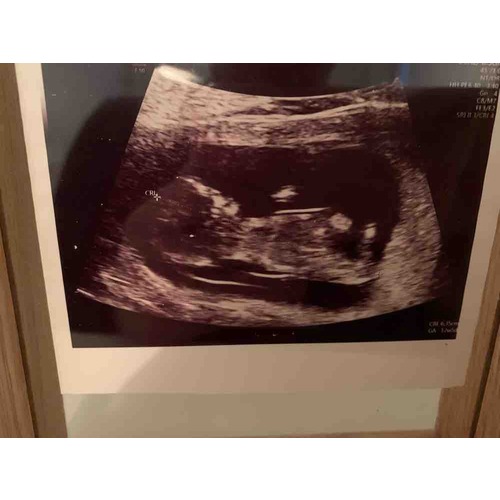

Ik heb hieronder een foto van ons kindje met T18 geplaatst. Ik vind dat hij er ‘afwijkend’ uitziet op de echo. Ik ben nu zwanger van een gezond jongetje en ik zie wel degelijk verschil als ik de echo’s met elkaar vergelijk. Ook als ik jouw echo bekijk, die ziet er in mijn ogen heel normaal uit allemaal.